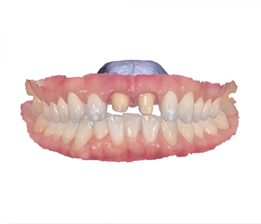

치아표면을 정확성 높게 재현

3차원 디지털 스캐너로 빠른 스캔!

Digital 02

• 첨단 디지털 장비 트리오스4 도입!

환자의 구강상태를 3D 스캔하여 치아의 변화나 문제점을 빠르게 진단 가능합니다. 또한, 간편한 스캔방식으로 환자의 불편함을 최소화합니다.